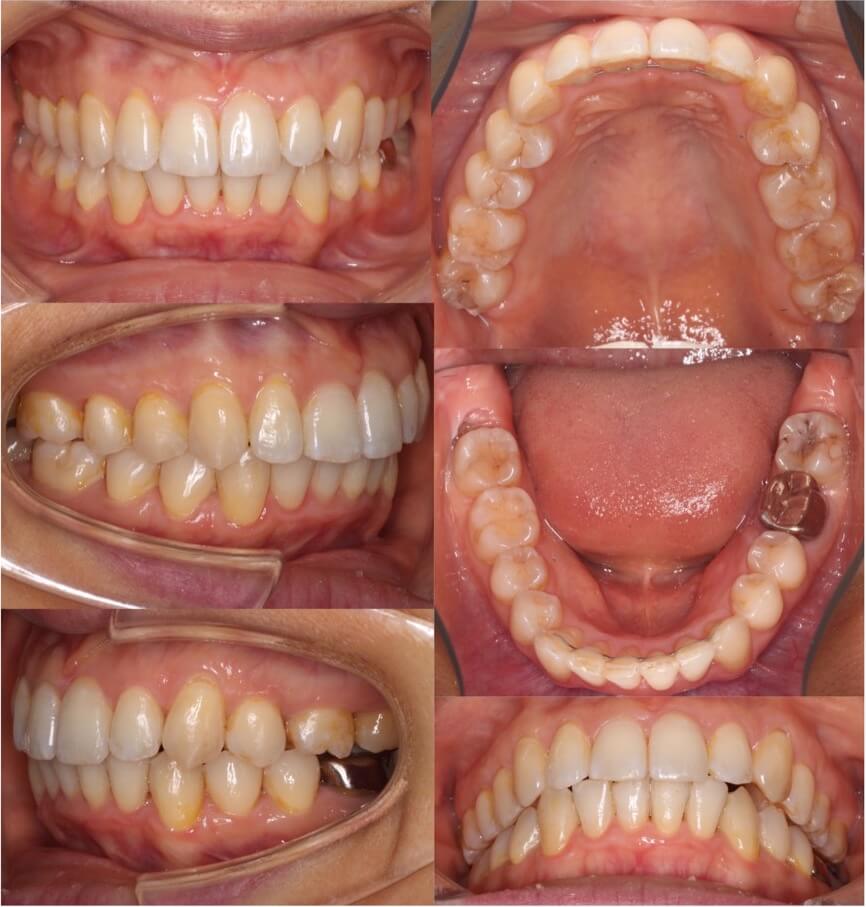

20代女性・マウスピース型装置

過蓋咬合の改善は見た目の変化は少ないのですが、口の中の歯並びの変化は大きいです。下の歯並びが見えるようになり正しいかみ合わせになりました。

<症例概要>

主訴:前歯のかみ合わせが悪い

年齢・性別:大学生女性

住まい:千葉県佐倉市

症状:過蓋咬合・右5番シザーズバイト・下顎叢生

治療方針:下顎前歯唇側傾斜による圧下

治療装置:マウスピース型矯正装置(アライナー装置)

アライナー枚数:43+27

治療期間:1年4か月

リテーナー:上下クリアタイプ

治療費用:990,000(税込)

代表的副作用:痛み・治療後の後戻り・歯根吸収・歯髄壊死・歯肉退縮

【治療シミュレーション】

主に下の歯並びを前方に倒しながら歯茎方向に沈め(圧下)させ、過蓋咬合を改善していきます。